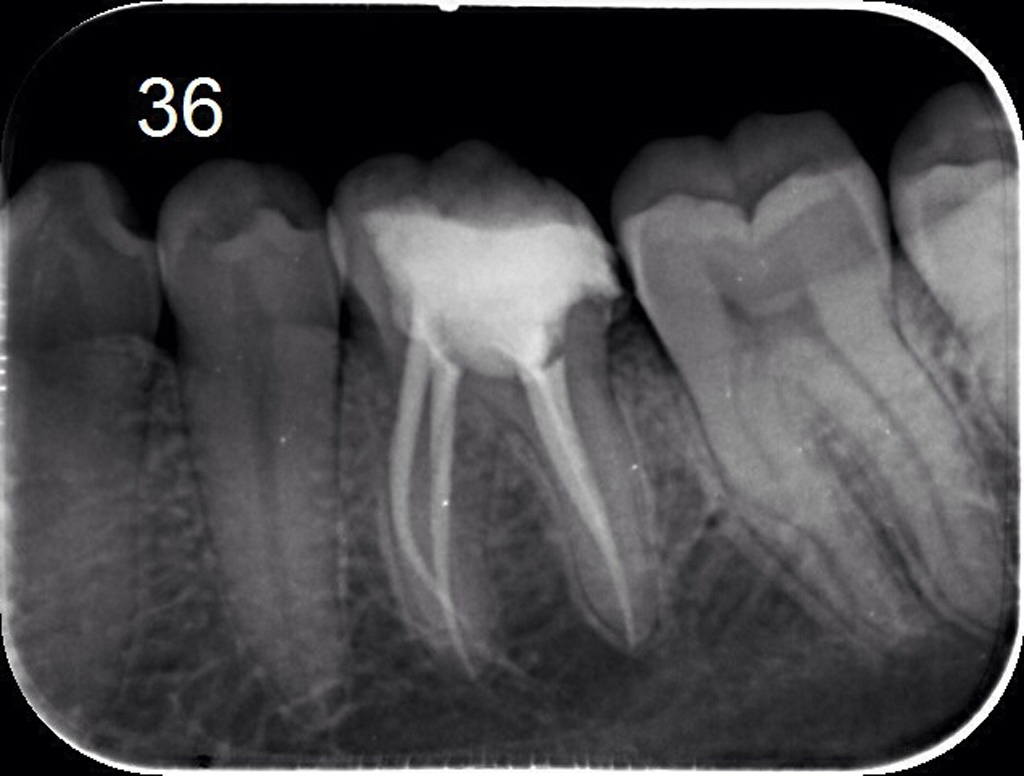

Lečenje zuba podrazumeva postupak uklanjanja nerva iz samog zuba. Naš tim se edukavao iz oblasti savremenih principa endodontske terapije i mašinske endodoncije kako bi svojim pacijetima ponudili najkvalitetnije usluge iz navedene oblasti.

Znanje i aparatura koju posedujemo omugućuje nam da obradu kanala korena zuba sprovodimo uoptrebom mašinskih rotirajućih instrumenata (ProtaperNext), irigansa propisanih od strane evropske asocijacije endodonata i savremnih tehnika punjenja kanala korena. Na taj način zubi su besprekorno izlečeni i traju dug vremenski period.